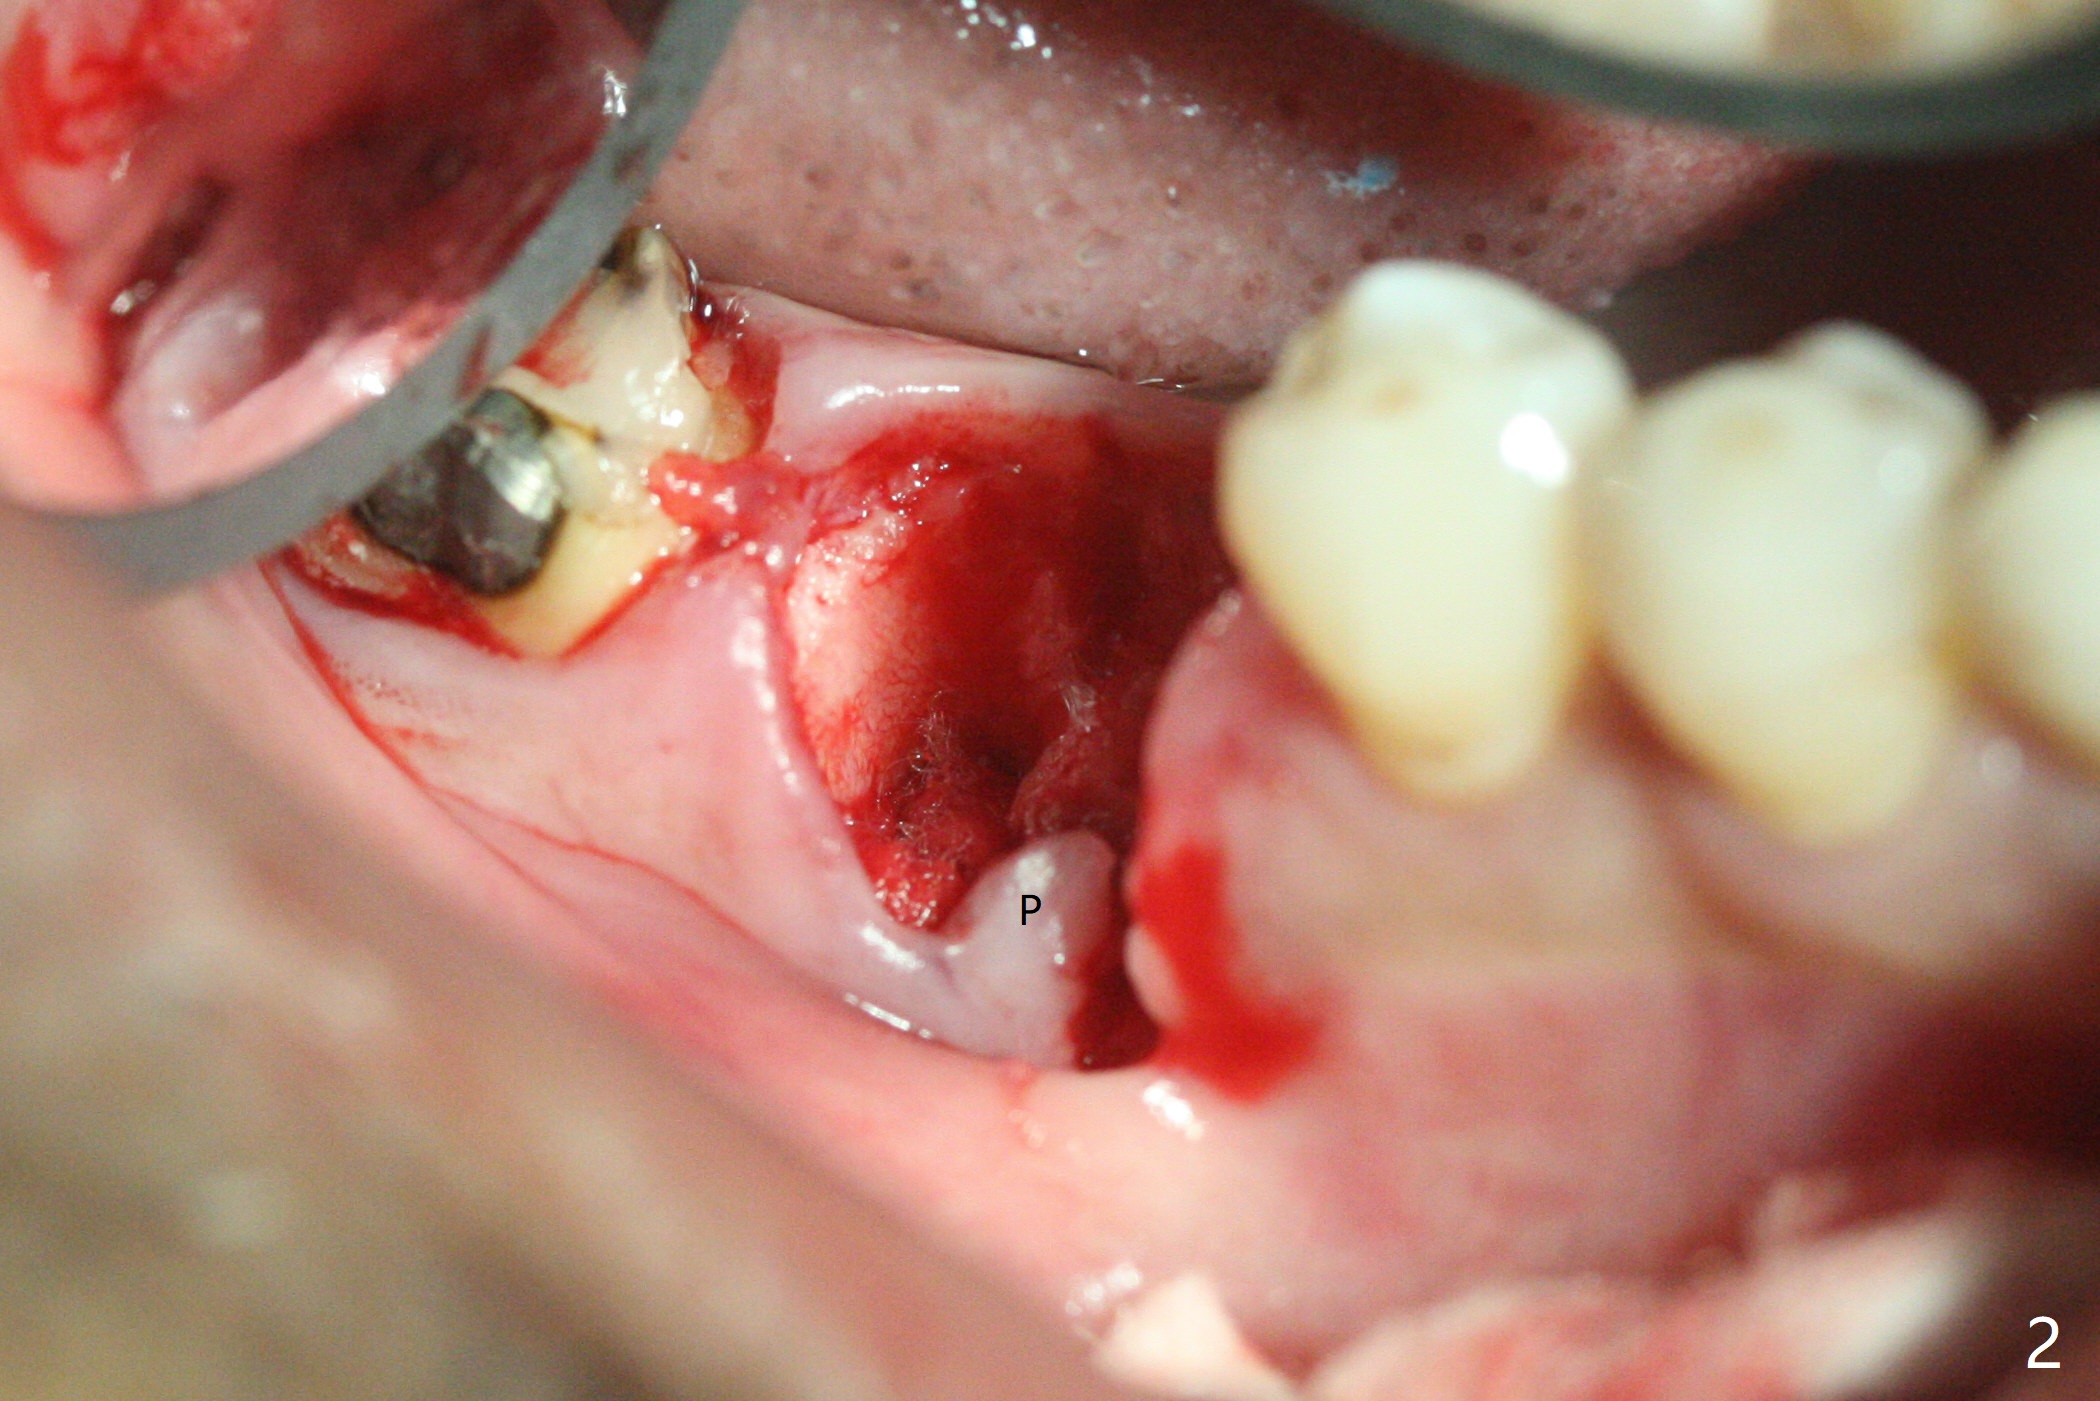

When the tooth #30 is extracted, the gingiva buccal to the septum (S in Fig.1,2 (P: papilla between the mesial and distal roots)) collapses. The latter is fixed with placement of a 4.5x11.5 mm implant (with guide), a 5.2x4(5) mm cemented abutment (Fig.3) and mixture of cortical bone (125μm – 850μm) and cortical/cancellous bone (.5-1 mm) with PRF (sticky bone, B in Fig.4-6). After placement of 2 pieces of PRF membrane over the bone graft, a temporary crown is fabricated to cover the buccal defect (Fig.7 T). Approximately 7.5 mm of the buccal threads are covered by the thick layer of bone graft (Fig.8 B). It is amazing to expect that the bone graft will turn into the buccal plate. It would be better if a narrower implant (4 instead of 4.5 mm) were placed more lingually or there were < 4 mm implant thread exposure (Fig.9). The gingiva reacts to the provisional nicely 7 days postop (Fig.10). The provisional will be removed for modification in 1 month. The patient complains of bad smell from the provisional 2 weeks postop. The provisional is removed. The distal socket (Fig.11 D) is healing, whereas the buccal bone graft (Fig.12 B) seems not have been vascularized. Pedicled flaps (I) should be transferred to cover the buccal bone graft. The margin of the provisional is polished, becomes short, and covered by periodontal dressing, which dislodges 2 days later. One week later, granulation tissue is forming apically with use of oral antibiotic and water jet (Fig.13 *). The bad smell reduces. The superficial loose bone graft changes colar and becomes detached 1 month 10 days postop. The temporary crown with the shortened buccal shelf is reseated for self cleansing or reapplication of PRF if needed (Fig.14).